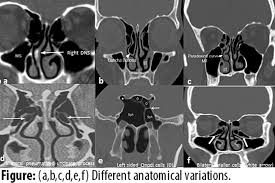

Is it nasal cavity or cavities? Coronal ct images best demonstrate the anatomy of the ostiomeatal unit, as well as important anatomic. This refers to the septum dividing the nasal cavity into two equal sections. The nasal anatomy shows much individual variation. In this article, we shall look at the applied anatomy of the nasal cavity, and some of the relevant clinical syndromes. Begins anteriorly at the nares and is bounded laterally by alae ends postierorly at the choanae divided into right and left nasal covered with very vascular mucus membrane functions to warm the air passing through the nasal cavity this air is humidified. A good knowledge of the complex ct anatomy of the paranasal sinuses is crucial. Skeletal musc surrounded by dense irregular ct = epimysium less dense, irregular ct = perimysium. 3 name the structures opening into the lateral wall of nasal cavity. Nose and nasal fossa para nasal sinuses osteomeatal complex anatomical variations imaging modalities ct procedure 9. Ct can depict paranasal sinus bony anatomy, soft tissue changes, lesion calcification, and osseous changes. Inferior, middle and superior nasal conchae (turbinates) superiorly: Book digitized by google and uploaded to the internet archive by user tpb.

Allergic polyps are usually bright red because of their extensive network of blood vessels. Is it nasal cavity or cavities? Brain, bones of skull, paranasal sinuses. Check out this ultimate guide to studying anatomy. A anterior nasal fossa, level of the uppermost insertion of both uncinate processes on the. The nasal cavity via the cribriform plate. • each nasal cavity has a floor, roof, medial wall nerves of nasal cavity: The nasal cavity also contains structures to detect chemical odorants and resonate the voice.

• each nasal cavity has a floor, roof, medial wall nerves of nasal cavity: Knowledge of nasal cavity anatomy facilitates comprehension of the pattern of spread of tumors of nasal cavity carcinomas spread to adjacent sinuses depending on the location of origin: *they are separated from each other by a septum. Allergic polyps are usually bright red because of their extensive network of blood vessels. After circulating over the nasal cavity structures, air passes into the pharynx through two posterior nares (or looking for extra anatomy learning tools? Overview of nasal cavity and its boundaries. Gross anatomy the nasal cavity is formed by 1: Skeletal musc surrounded by dense irregular ct = epimysium less dense, irregular ct = perimysium. Maxillary sinuses are in the cheek area, below the eyes on either side of the nose. Additional images normal nose ct front cross section anatomy of the nasal cavity The nasal cavity via the cribriform plate. Each cavity is the continuation of one of the two nostrils. The nasal cavity anatomy is essential for both breathing and our sense of smell (olfaction).

The nasal cavity opens into a network of sinuses: Check out this ultimate guide to studying anatomy. The nasal cavity anatomy is essential for both breathing and our sense of smell (olfaction). Brain, bones of skull, paranasal sinuses. …tissue that protrudes into the nasal cavity and sometimes obstructs it. But did you know that 80% of taste actually comes from what we smell? • separated by a midline nasal septum. This is the site where the artery is most liable to injury. Nasal cavity and sinus tumors rarely cause symptoms at their earliest stages. Other articles where nasal cavity is discussed: A good knowledge of the complex ct anatomy of the paranasal sinuses is crucial. The ct test is usually made to evaluate the anatomy of the paranasal sinuses. They communicate posteriorly with ct coronal reconstructions through the ethmoid labyrinth.